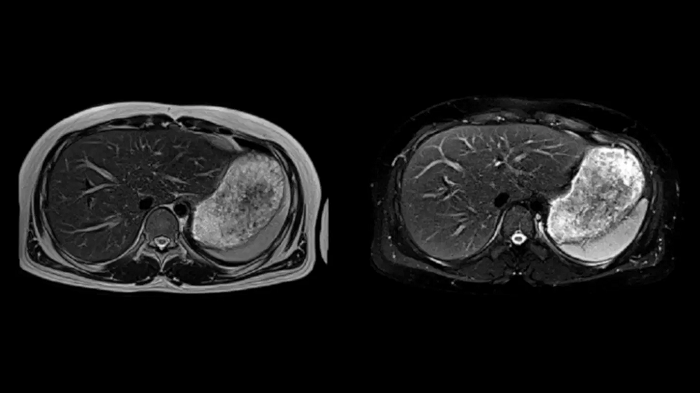

Abdomen

T1 VIBE Dixon with CAIPIRINHA

Get benefitted from Siemens Healthineers dedicated CAIPIRINHA acceleration to gain a complete abdominal volume within a single breath-hold. The Dixon technique offers outstanding fat water separation for a flawless representation of the abdominal anatomy.

T2 BLADE

T2 motion insensitive abdominal imaging with BLADE results in outstanding outcomes, regardless of the orientation or if fat saturation is needed.

MAC-ID: 7aaaa0165. Image Credit: Siemens Healthineers